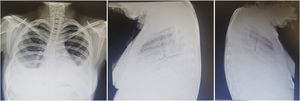

Prognosis. Historic series report a mortality of up to 50%; the most recent series reported a mortality rate of 40%.28 Although it is an uncommon complication, lupus pneumonitis during pregnancy and the postpartum has been associated with especially adverse outcomes.29–31 The predominance of lymphocytes in BAL is associated with a more favorable course, whereas the predominance of eosinophils or neutrophils is associated with a higher rate of mortality. In up to 50% of the survivors, interstitial infiltrates and abnormal respiratory function persist, with risk of progression to chronic interstitial pneumonitis.3,14Fig. 3 shows the findings in pneumonitis and pulmonary hypertension.

A 22-year-old man with a twin brother with systemic lupus erythematosus. Both showed evidence of Schnitzler syndrome (intermittent episodes of fever, urticaria, abdominal pain, angioedema, arthritis). He had a 2-month history of progressive dyspnea even on minimum exertion, polyarthritis, hypertension, mechanical edema and, on the preceding days, cough and increased dyspnea. Exploration revealed Chávez’ pulmonary complex and right basal condensation syndrome; radiograph showing evidence of pulmonary hypertension, 4 arches, right basal pneumonitis and homolateral effusion. He was diagnosed with lupus pneumonitis, which was managed with prednisone at 0.5mg/kg body weight/day and cyclophosphamide, with a satisfactory response.